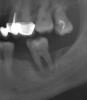

kmatv Опубликовано 14 июля, 2011 Поделиться Опубликовано 14 июля, 2011 (изменено) А что в такой ситуации (почти похожей) посоветовали бы гуру имплантации? А что в такой ситуации (почти похожей) посоветовали бы уру имплантации? 3 сегмент Изменено 14 июля, 2011 пользователем kmatv Ссылка на комментарий

Bier Опубликовано 14 июля, 2011 Поделиться Опубликовано 14 июля, 2011 для начала я бы рассмотрел целесообразность восстановления второго моляра. Ссылка на комментарий

m.d.n Опубликовано 14 июля, 2011 Автор Поделиться Опубликовано 14 июля, 2011 А что в такой ситуации (почти похожей) посоветовали бы гуру имплантации? А что в такой ситуации (почти похожей) посоветовали бы уру имплантации? 3 сегментудаление кюретаж - формирование сгустка - можно с каркасником каким нить- или по богатому - заполнить дефект бисульфатом кальция BondBone, Ссылка на комментарий

Bier Опубликовано 14 июля, 2011 Поделиться Опубликовано 14 июля, 2011 там судя по снимку (я не уверен, но интуиция подсказывает) нету вестибулярной стенки кости, а может и язычной.в таком раскладе губка не прокатит, каркас нужен. Ссылка на комментарий

kmatv Опубликовано 15 июля, 2011 Поделиться Опубликовано 15 июля, 2011 (изменено) Если на снимок присмотреться есть стенки. Активного гноетечения не было, но воспаление (подострое) все же есть. В общем удалил-поствил блок, без фиксации, встал на ура. Сейсчас там уже винт. Делал так уже не один раз- результа оч. хороший, можно его рассматриват как элемент объемного моделирования кости. Изменено 15 июля, 2011 пользователем kmatv Ссылка на комментарий